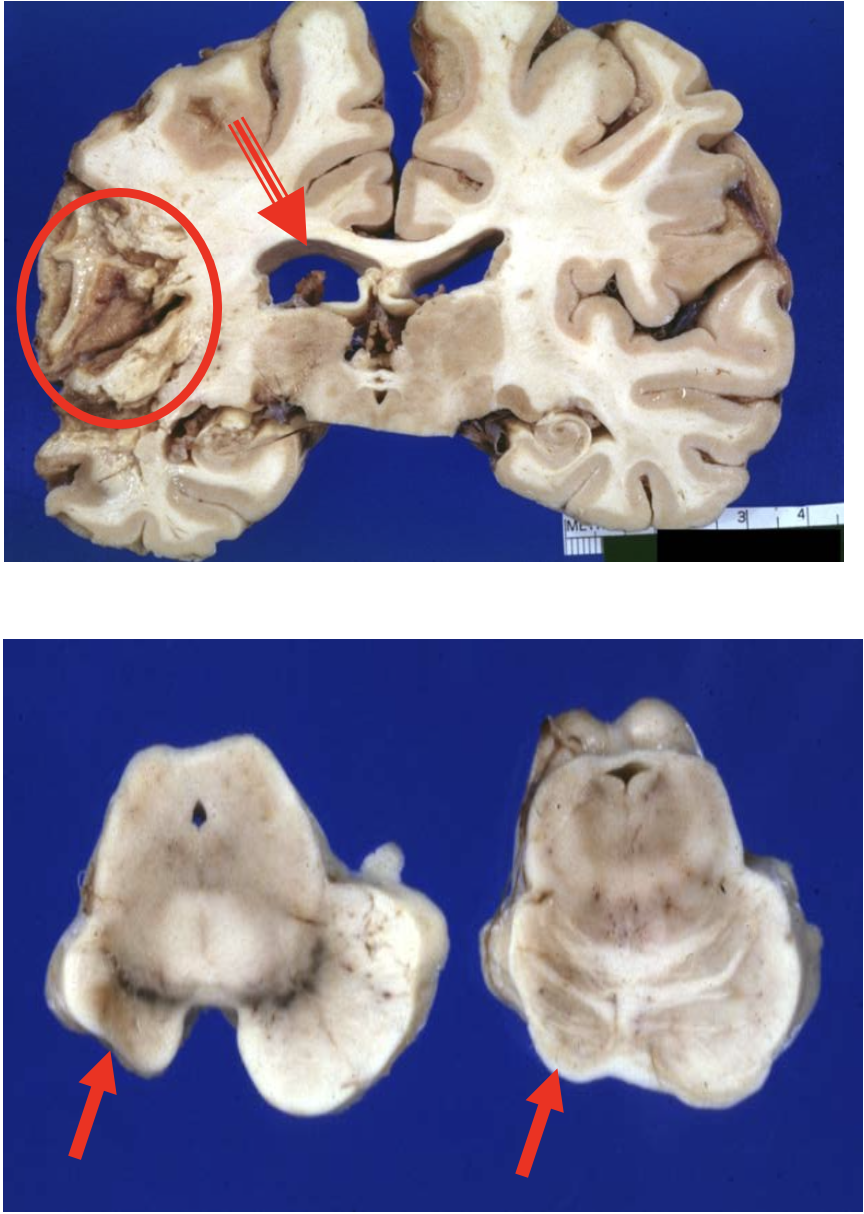

Chronic cortical ischemic stroke

Aftermonths,allthat remains is a cystic cavity surrounded by gliotic tissue with glial strands (circle)

-There is compensatory (ex- vacuo) ventricular enlargement (open arrow)

Wallerian degeneration of the cerebral peduncle and corticospinal tract in the pons. (arrows)